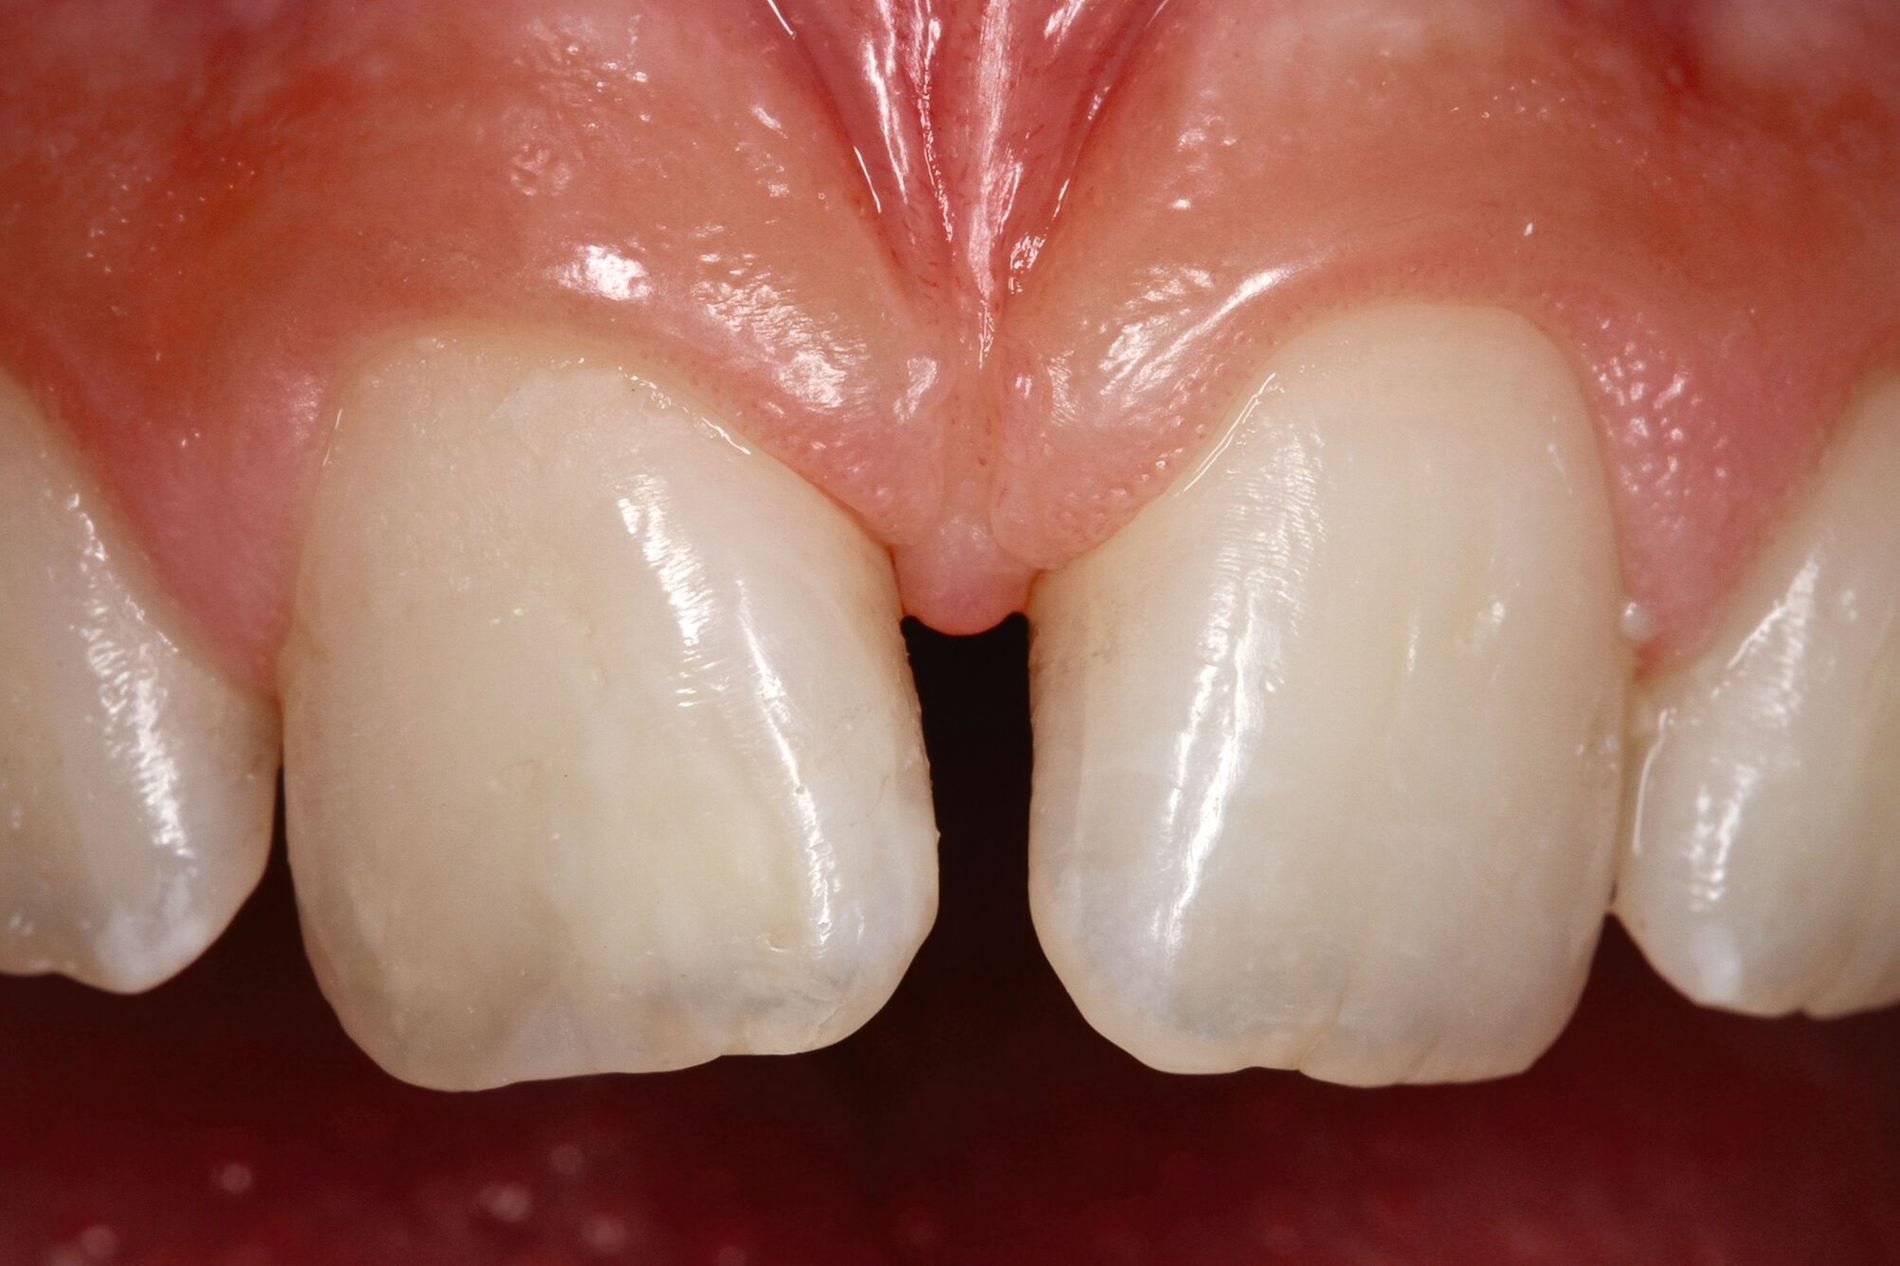

Wenn die Lückenversorgung durch eine Transplantation (siehe Teil 4 der Fortbildung „Dentales Trauma“: Chirurgische Aspekte) oder einen kieferorthopädischen Lückenschluss (siehe Teil 5 der Fortbildung „Dentales Trauma“: Kieferorthopädische Aspekte) vorbereitet wurde, beschränkt sich die restaurative Versorgung auf eine Formkorrektur der Zähne. Diese kann – je nach Situation und Präferenz des Behandlers – mit direkten (Abbildung 4) oder mit (minimalinvasiven) indirekten Restaurationen (Veneers, Teilkronen) erfolgen. Gerade bei jungen Patienten muss allerdings berücksichtigt werden, dass im Zuge der passiven Eruption [Mele et al., 2018] Veränderungen des Gingivaverlaufs an den restaurierten Zähnen zur Exposition der Restaurationsränder führen und eine neue Versorgung nach mehreren Jahren erforderlich machen können.